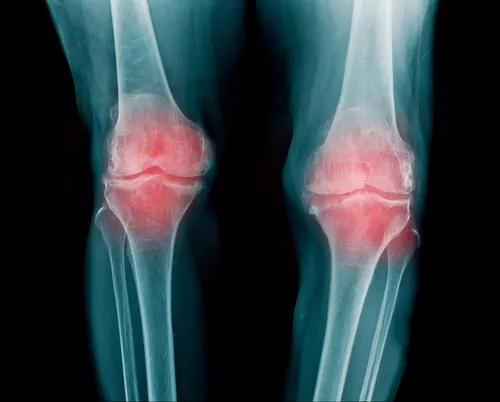

Una articulación es una zona en la que se juntan los extremos de dos o más huesos o un hueso y un cartílago. Gracias a ellas el cuerpo puede moverse; hacen posible que piernas, brazos y espalda se flexionen y giren.

Entre los huesos que forman la articulación existe un tejido elástico y flexible, el cartílago articular. El cartílago evita la fricción entre los huesos al actuar como un sistema de amortiguación.

La articulación está rodeada por una “bolsa articular” que sostiene todo este sistema. Esta bolsa está reforzada por ligamentos que impiden que las articulaciones se dañen fácilmente.

Las articulaciones pueden verse afectadas por diferentes enfermedades que impactan sobre ellas. Uno de los síntomas que aparece primero es el hormigueo las articulaciones: en manos, pies, brazos y piernas.